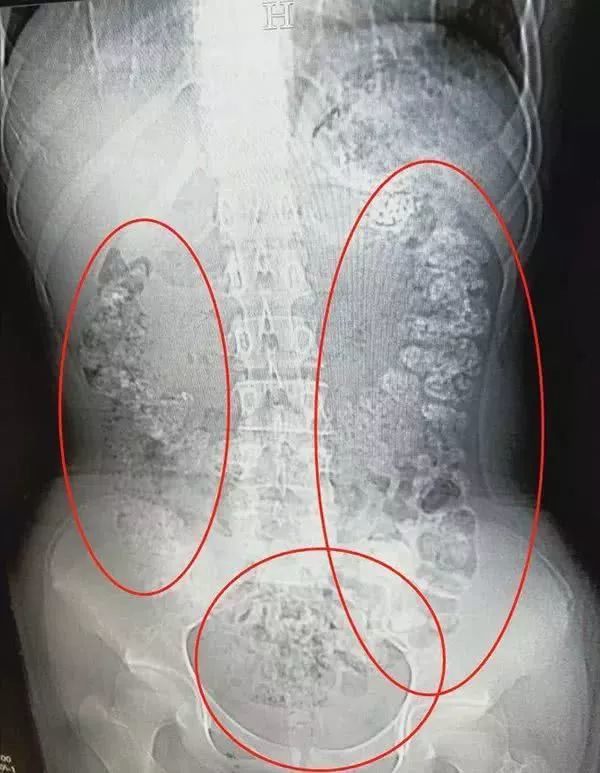

14岁女孩从胃肠到肛门密密麻麻...

来自浙江的女孩小沈(化名),在父母的陪同下来到浙江诸暨市人民医院急诊。小沈跟医生说自己肚子疼,有好几天无法排便,也吃不下东西。

于是,在医生的安排下,小沈做了腹部的CT。本来以为是普通的肠胃病,可没想到检查结果,让医生一惊:

患者胃部、横结肠、升结肠

降结肠、乙状结肠

一直到肛门

全都是颗粒状阴影

足足有百余颗之多

这么多颗粒状阴影究竟是什么东西呢?在医生的问询下,患者小沈才道出了实情。原来小沈5天前喝了一杯珍珠奶茶,而喝下去的珍珠,没有被消化掉,堆积在小沈的肠胃处。